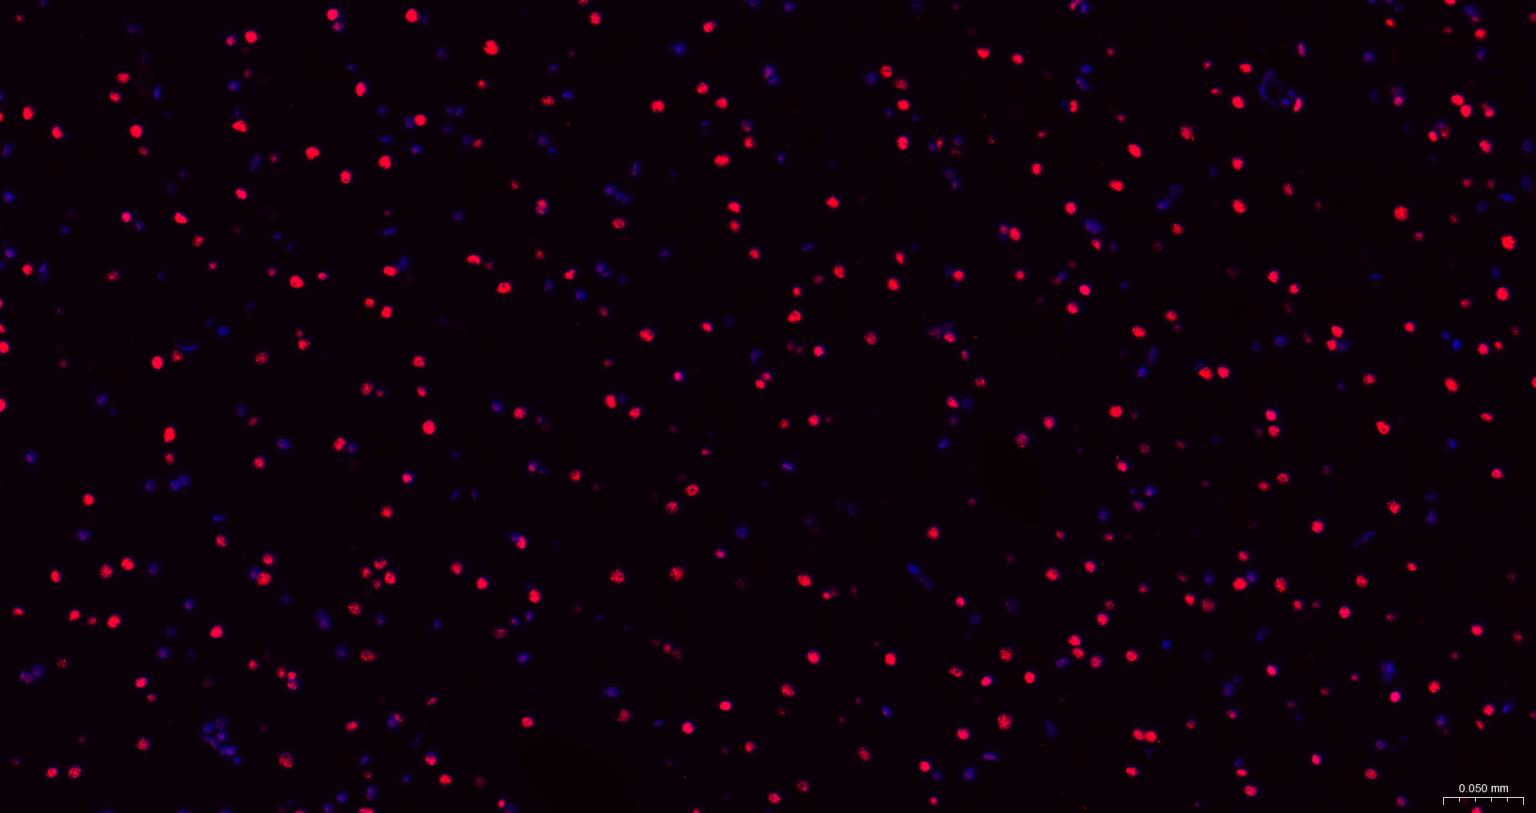

Paraformaldehyde-fixed, paraffin embedded Human Cerebrum; Antigen retrieval by boiling in sodium citrate buffer (pH6.0) for 15 min; The section was incubated with TARDBP Monoclonal Antibody, Unconjugated (bsm-60837R) at 1:200 overnight at 4°C. Followed by conjugated Goat Anti-Rabbit IgG antibody (Red, bs-0295G-BF594), DAPI (blue, C02-04002) was used to stain the cell nuclei.